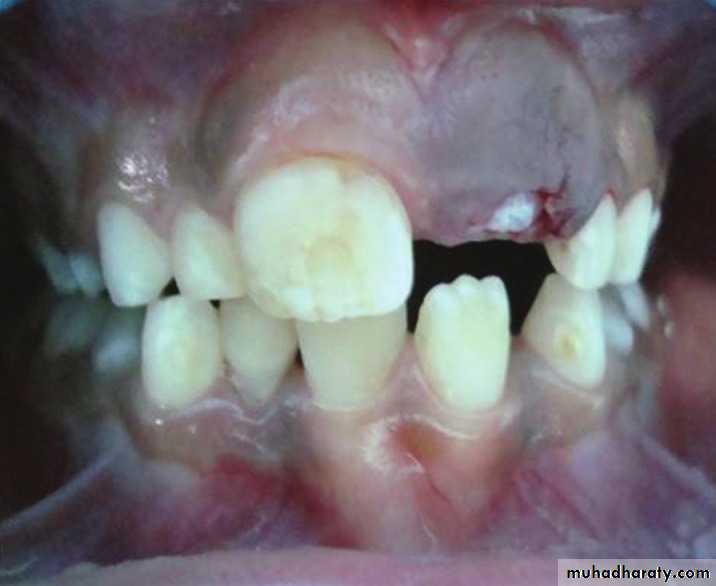

A 11-year-old female with swelling on the right side.

impacted canine

Ameloblasoma*Non-metastasizing tumor originating from remnants of the odontogenic epithelium of the enamel organ or dental lamina. *Associated with the crown of impacted teeth.

*80% located in the bicuspid & molar regions.

*Shape: is either unicystic or soap bubble-like lesion, Expansile, *Tooth migration is common,teeth in the area are vital.

*Adjacent teeth displaced, loosened , often resorbed

Extensive expansion in all dimensions

Maxillary lesions can extend into the paranasal sinuses, orbit or base of the skull.

Male > female.

Age; > 30 years